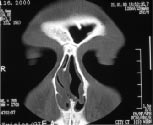

| Рентген | Носовые пазухи |

| КТ | Носовые пазухи |